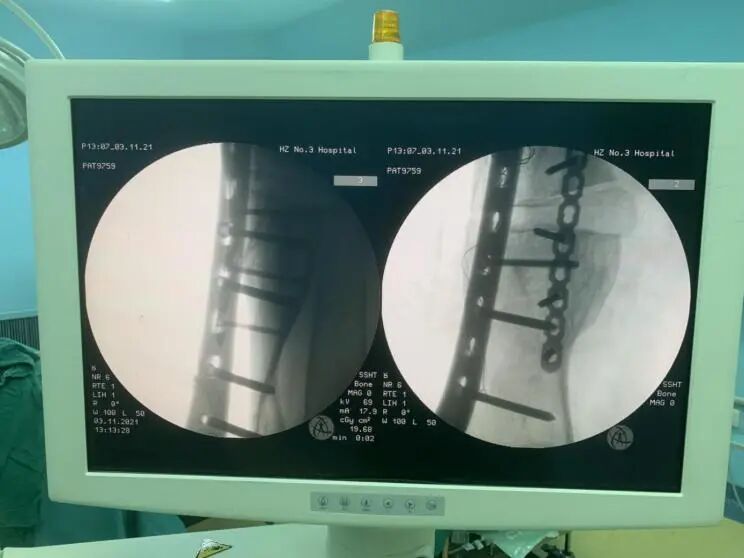

術(shù)中,醫(yī)療團(tuán)隊按照預(yù)定手術(shù)思路,首先沿左大腿中下段外側(cè)縱形作皮膚切口,安裝股骨前方截骨導(dǎo)板,用擺鋸沿截骨導(dǎo)板截斷股骨畸形最大處,預(yù)留股骨干外側(cè)部分皮質(zhì)。然后用撐開器沿截骨端將其撐開并放置內(nèi)側(cè)楔形導(dǎo)板,在C臂機(jī)透視下見經(jīng)截骨矯形后現(xiàn)股骨干向內(nèi)、向后成角畸形基本恢復(fù),力線基本糾正。最后進(jìn)行左側(cè)股骨鋼板內(nèi)固定術(shù)+左側(cè)髂骨切除術(shù)用作移植物+左側(cè)股骨植骨術(shù)+左側(cè)股骨人工骨植骨術(shù)。整個手術(shù)過程非常順利。

術(shù)中截骨后影像

術(shù)中鋼板螺釘固定后影像